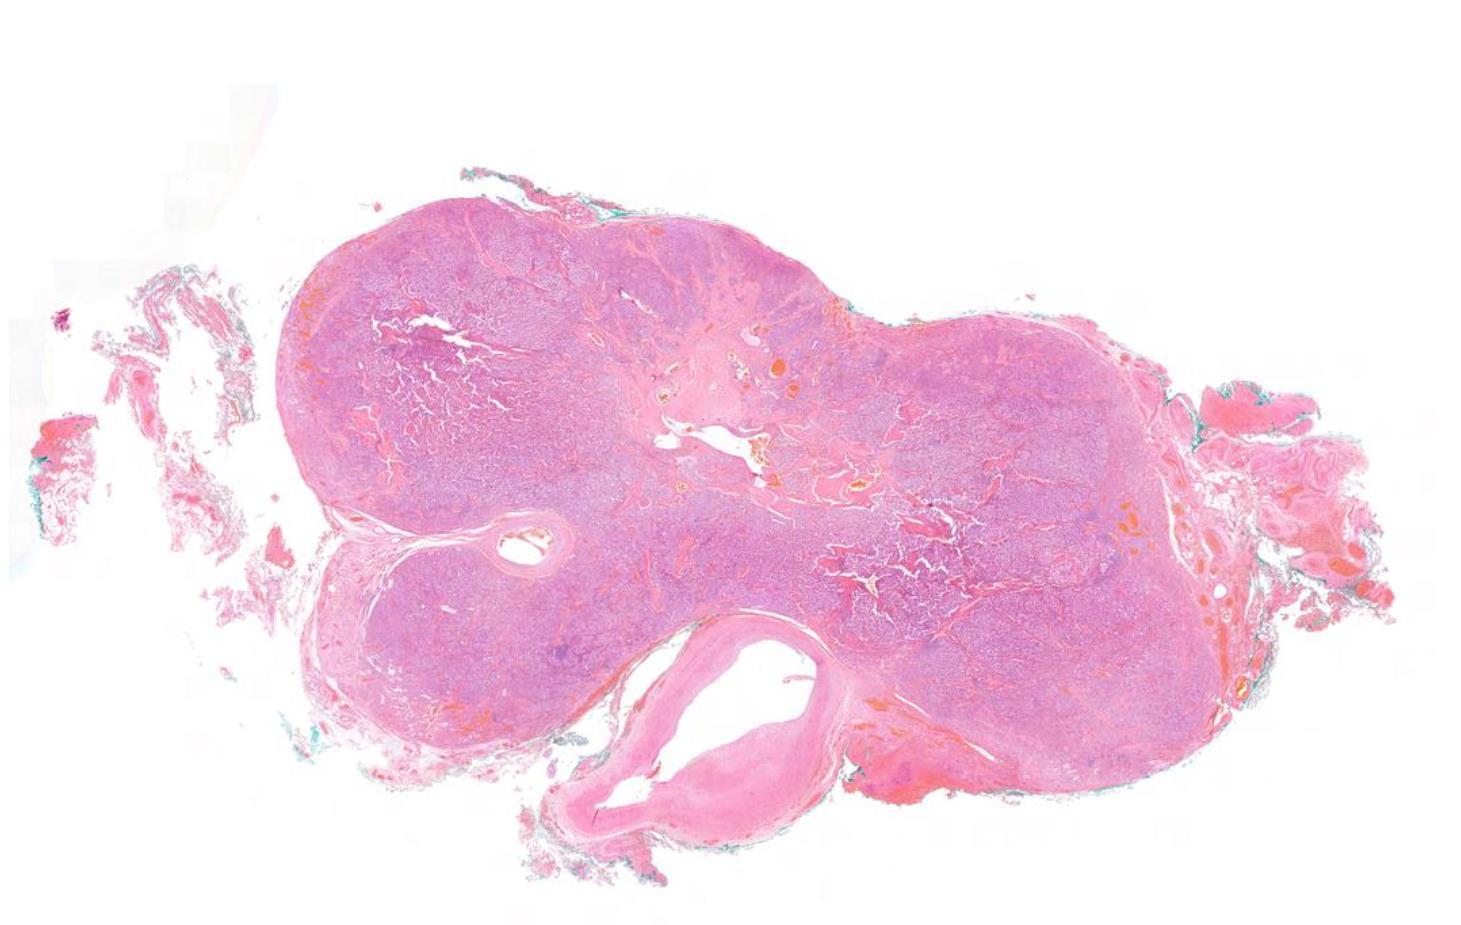

Case 24 55-year-old, Male Parotid Swelling

??

Case 24 Diagnosis

Pleomorphic adenoma with ossification and atypia